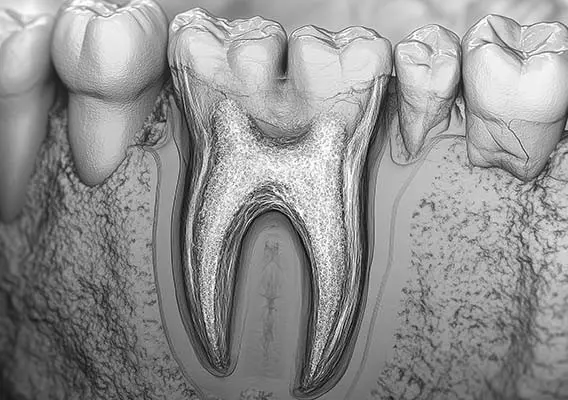

W tym wydaniu m.in: zapalenie przyzębia a ryzyko otępienia, gojenie zmian okołowierzchołkowych, okolica przyszyjkowa jako kompleksowe spojrzenie kliniczne, WawaDent 2024, by-pass złamanego narzędzia.